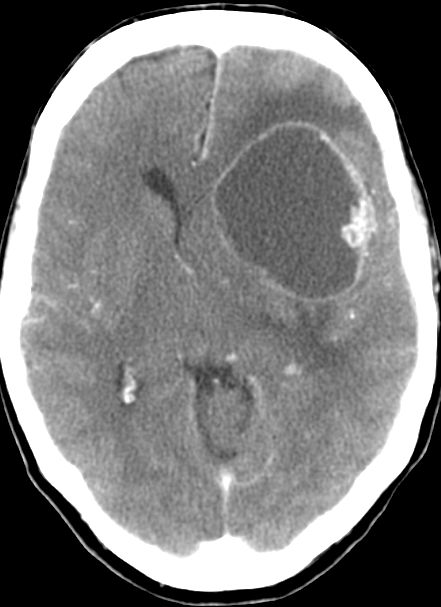

| große zystische Hirnmetastase | asymptomatisches Adenokarzinom des linken

Hauptbronchus mit primärer Hirnmetastase![]() ![]() |